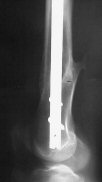

THX, initial images are

1,

2.

KEMMD> - Your last posted case: how is possible to have secure fixation with

KEMMD> applied construct without additional casting, bracing or Ilizarov?

At that moment we had in stock only the 10 mm solid nails so of course there was no idea about early weight bearing. But it was quite enough for early knee ROM excersises (see attached). Two locking screws through the distal block provided that.